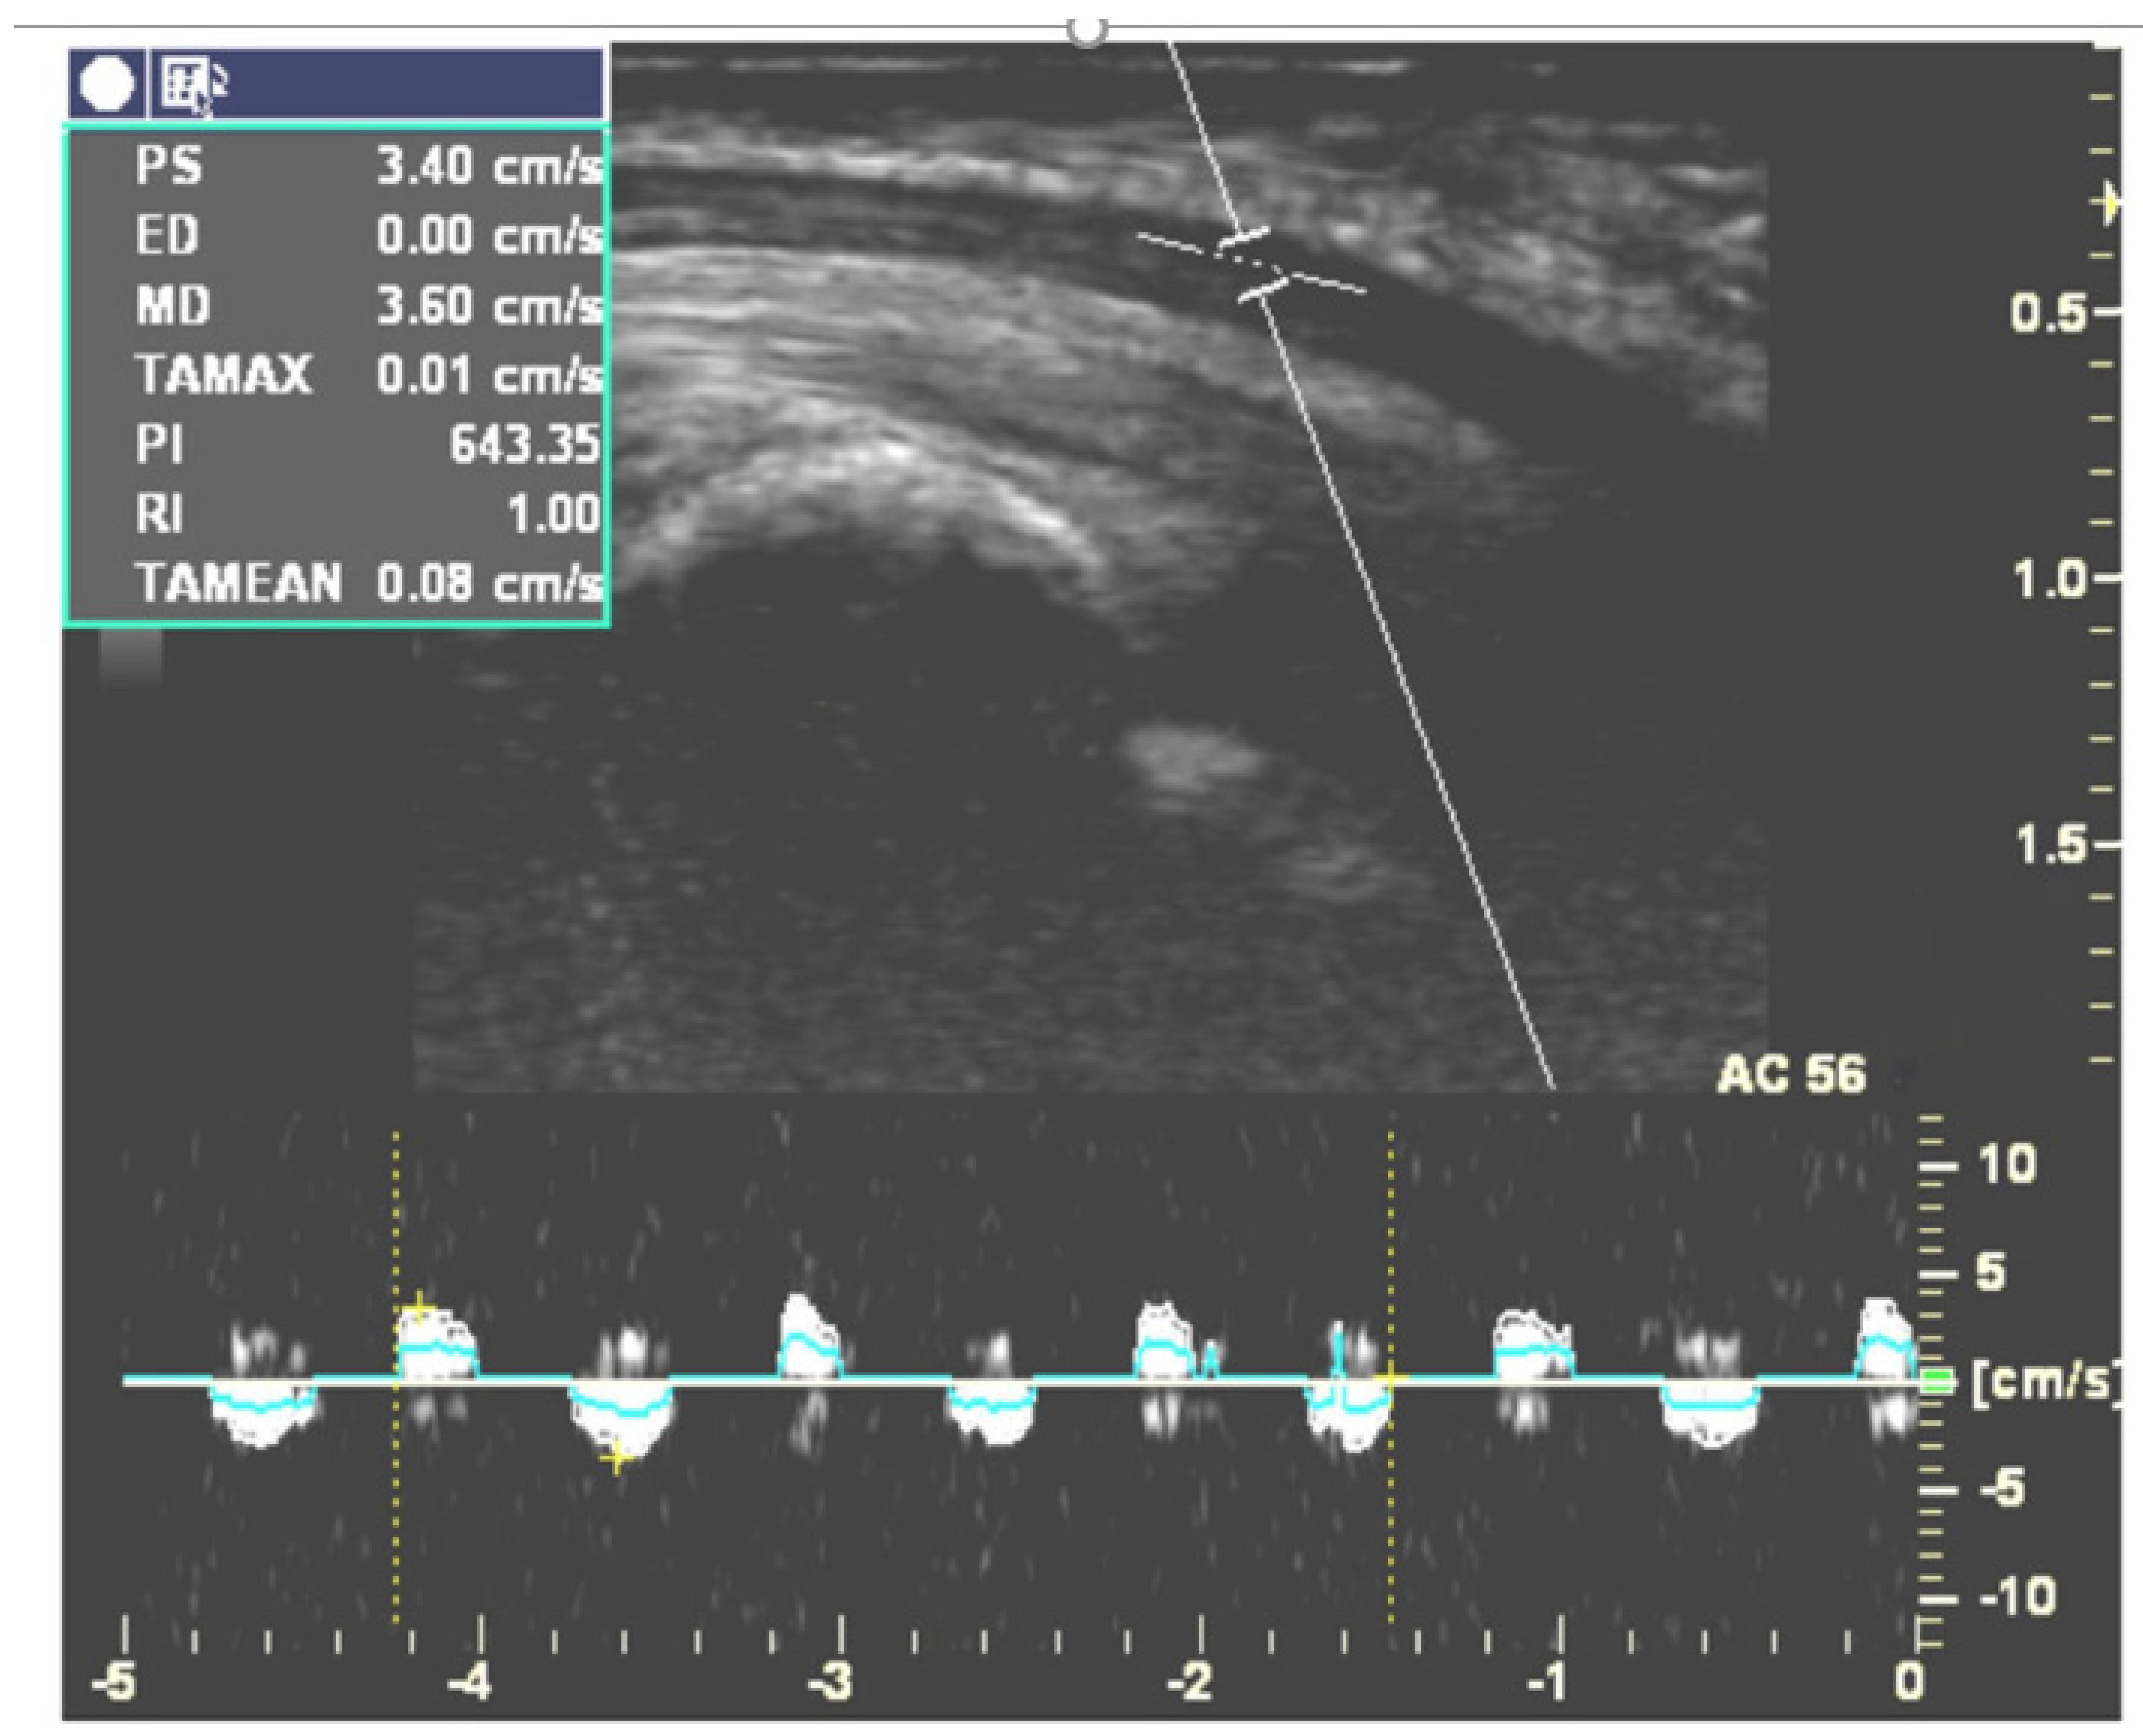

Two independent researchers collected the relevant data from each eligible article, including the authors, published year, average age, sex distribution, number of wrists in each group, diagnostic reference for the CTS group, severity of the CTS group, sites of ultrasonic measurement, and hand or finger postures and movements while performing ultrasonography. Information regarding the ultrasonic analysis methods including speckle tracking algorithm, cross-correlation (CC) algorithm, multilevel block-sum pyramid (BSP) integrate algorithm, duplex Doppler (Figure 2) and parameters (actual MN displacement distance, MN displacement in two directions, normalized displacement, etc.) were also retrieved.

Five studies targeting longitudinal gliding of the MN are described in Table 4. Two [30,33] of them used duplex Doppler to evaluate longitudinal gliding of the MN by adjusting the Doppler sample volume indicator to lie within the MN (Figure 2). They recorded the Doppler waveform while subjects continuously moved their fingers and calculated the area under the Doppler waveform in the velocity-time integral (VTI) spectrum. This area represented the amount of longitudinal MN gliding during each cycle of finger movement [55]. Hough et al. found that CTS patients had less MN gliding than healthy controls during elbow extension but not during elbow flexion [30]. Liu et al. [33] measured longitudinal MN gliding in both the neutral and 30 degree wrist extension positions. Their results revealed that the ratio of the gliding of the MN to the flexor tendon was significantly smaller in CTS patients than in healthy volunteers. They also found that gliding of the MN was significantly increased while extending the wrist joint to 30 degrees in CTS patients [33]. The other three studies recorded B-mode dynamic ultrasonography while subjects performed the target movements and used a cross-correlation algorithm or speckle-tracking algorithm to evaluate MN gliding frame-by frame [29,31,32]. For example, Erel et al. [29] analyzed longitudinal MN gliding at the forearm level during passive motion of the metacarpophalangeal joint, but their results did not demonstrate a significant difference in MN gliding between the CTS and control groups. In contrast, Filius et al. [31] demonstrated less longitudinal MN gliding in CTS patients. Filius et al. also published another article [32] exploring the relationship between tendon excursion velocity and longitudinal MN gliding. They found that the higher the moving velocity of the fingers, the greater the MN glided; moreover, MN gliding was reduced in the CTS group whenever fingers were moving at high or low speed.

Figure 2. Doppler waveforms for measuring longitudinal MN gliding during active flexion and the extension cycle of the index finger at a speed of one time per second. (This figure was adapted from Liu et al. [33]).